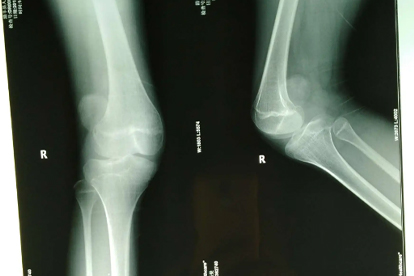

1、X线平片

X线平片可显示髌骨位置异常、股骨滑车发育不良等骨性结构问题。通过膝关节正侧位、轴位片评估髌骨轨迹,测量髌骨倾斜角及适合角。该检查对明确脱位方向及是否合并骨折有重要价值,是复发性髌骨脱位的首选基础检查。